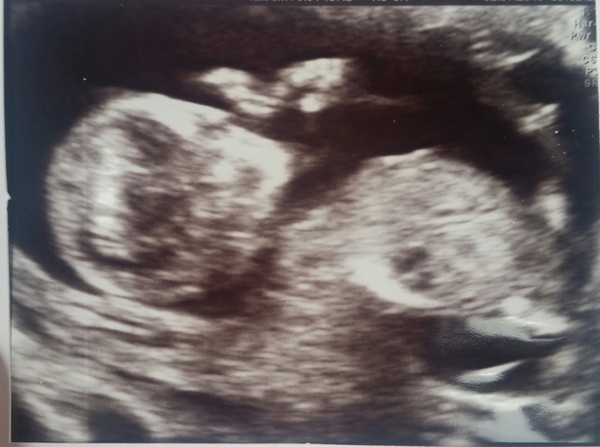

Also I say girl based on the nice round skull, but will be interested to see if you're right - I've felt mine's a girl all the way through, but got a lot of boy votes on here from my 12 week scan! Hope the scan goes well